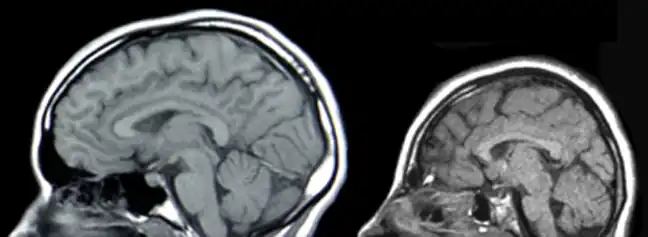

a) Two newborns with microcephaly b) brain computed tomography scan

a) Two newborns with microcephaly b) brain computed tomography scan Neural scans of a normal-sized skull (left) and a case of microcephaly

Neural scans of a normal-sized skull (left) and a case of microcephaly